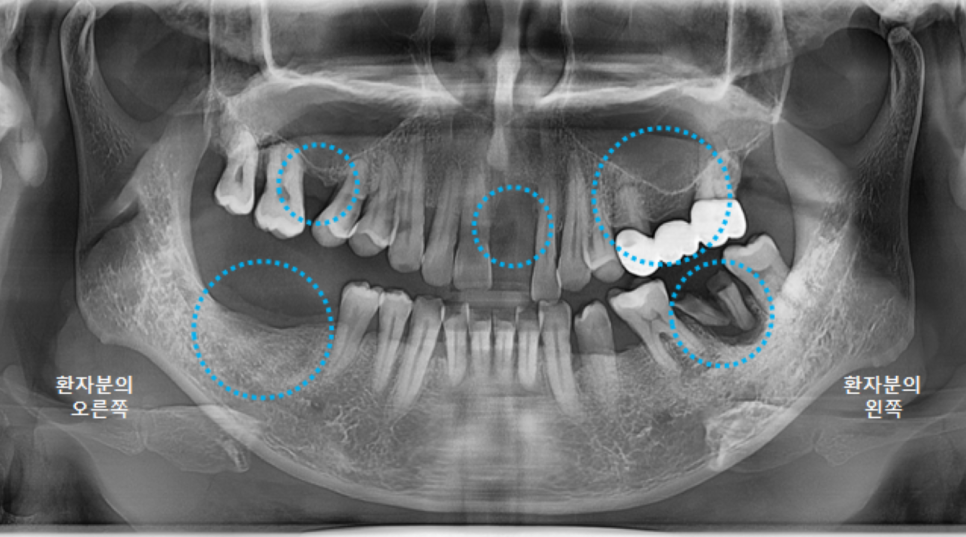

전체적인 구강 판단을 위해

파노라마 엑스레이 사진을 찍었습니다.

왼쪽 큰앞니도 빠져있지만,

오른쪽위 큰어금니, 오른쪽 아래 큰어금니도 발치된 상태였고,

왼쪽 위 브릿지 상태도 좋지는 않았습니다.

왼쪽 아래 큰어금니 하나는 뿌리만 남은 상태였어요.